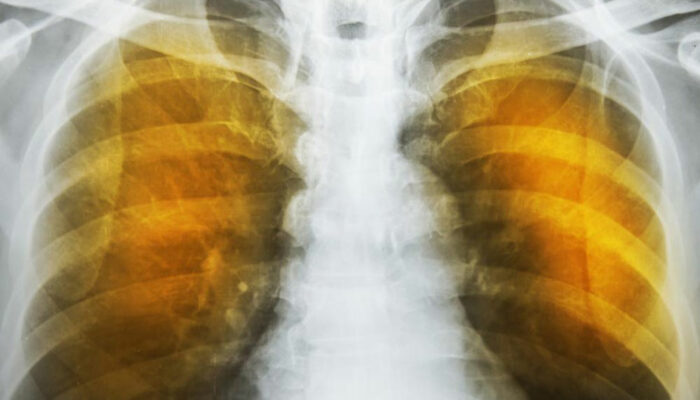

Emphysema is an oppressive respiratory disorder which results from the disintegration of the alveoli, i.e., the tissues where the interchange of gas with blood takes place. Destruction in any large scale will reduce the gas transfer area and the process of gas transfer itself, leading to oxygen starvation or hypoxia.